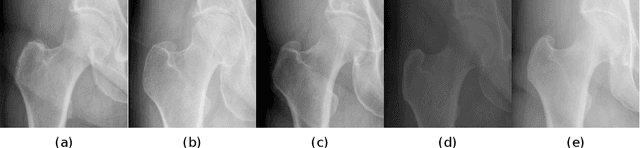

Abstract:Image landmark detection aims to automatically identify the locations of predefined fiducial points. Despite recent success in this filed, higher-ordered structural modeling to capture implicit or explicit relationships among anatomical landmarks has not been adequately exploited. In this work, we present a new topology-adapting deep graph learning approach for accurate anatomical facial and medical (e.g., hand, pelvis) landmark detection. The proposed method constructs graph signals leveraging both local image features and global shape features. The adaptive graph topology naturally explores and lands on task-specific structures which is learned end-to-end with two Graph Convolutional Networks (GCNs). Extensive experiments are conducted on three public facial image datasets (WFLW, 300W and COFW-68) as well as three real-world X-ray medical datasets (Cephalometric (public), Hand and Pelvis). Quantitative results comparing with the previous state-of-the-art approaches across all studied datasets indicating the superior performance in both robustness and accuracy. Qualitative visualizations of the learned graph topologies demonstrate a physically plausible connectivity laying behind the landmarks.